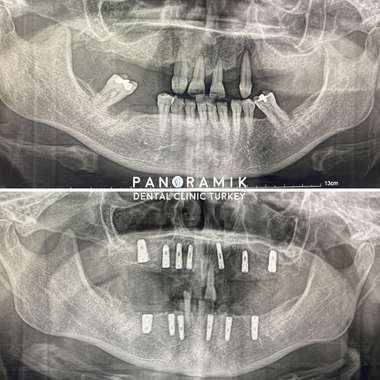

Image-1: Full mouth implants

The condition of having no teeth in the mouth is called complete edentulism. There are multiple treatment options for our patients who have no teeth. Implant treatment is one of these methods.

Implant in complete edentulism is the absence of any tooth in the mouth and the application of implant treatment in this case. After tooth loss, bone loss and related aesthetic, health and functional problems arise. In patients who have lost all their teeth for various reasons, 2 to 4 implants can be placed. Removable prostheses are prepared on these implants. The aim is to prevent the tooth from moving while talking, eating and even sneezing with implant supports. After the removable prosthesis option in implant treatment in total edentulism, the other option is fixed prosthesis. In this option, the prosthesis is glued onto the implant and a natural tooth appearance is obtained.

In the treatment of fixed implant or complete edentulism, the first examination is performed by your dentist. Then it is decided how many implants will be placed. At least 5 implants are placed, but this number varies according to the patient's systemic condition and bone level. The type of prosthesis is determined according to the number of implants. While 2-4 implants are used for removable prostheses, 5 or more implants should be placed for fixed prostheses.